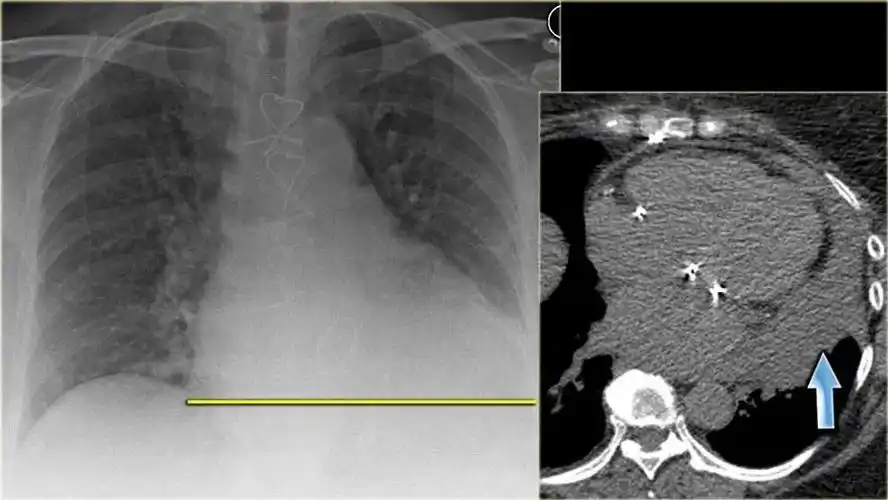

图4 肺泡性水肿ct扫描.双侧肺门气道病变几乎对称(有空气支气管征).

f,45,心源性肺泡性肺水肿.双肺内中带分布.

不同类型肺水肿的ct表现